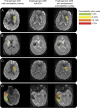

Objective: This study sought to confirm the relationship between the degree of blood-brain barrier (BBB) damage and the severity of intracranial hemorrhage (ICH) in a population of patients who received endovascular therapy.

Methods: The degree of BBB disruption on pretreatment MRI scans was analyzed, blinded to follow-up data, in the DEFUSE 2 cohort in which patients had endovascular therapy within 12 hours of stroke onset. BBB disruption was compared with ICH grade previously established by the DEFUSE 2 core lab. A prespecified threshold for predicting parenchymal hematoma (PH) was tested.

Results: Of the 108 patients in the DEFUSE 2 trial, 100 had adequate imaging and outcome data and were included in this study; 24 developed PH. Increasing amounts of BBB disruption on pretreatment MRIs was associated with increasing severity of ICH grade (p = 0.004). BBB disruption on the pretreatment scan was associated with PH (p = 0.020) with an odds ratio for developing PH of 1.69 for each 10% increase in BBB disruption (95% confidence interval 1.09-2.64), although a reliably predictive threshold was not identified.

Conclusions: The amount of BBB disruption on pretreatment MRI is associated with the severity of ICH after acute intervention. This relationship has now been identified in patients receiving IV, endovascular, and combined therapies. Further study is needed to determine its role in guiding treatment.